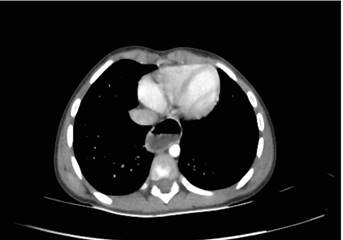

Reiteradas consultas en servicios de urgencias donde se le indicaron tratamiento sintomático con antieméticos, con persistencia de la sintomatología. Ingresó en el Hospital Pediátrico, Centro Hospitalario Pereira Rossell (HP-CHPR), para continuar valoración diagnóstica y terapéutica. Durante la hospitalización se identificaron regurgitaciones inmediatas a la alimentación con sólidos y líquidos, pero de forma más marcada con sólidos, sin elementos patológicos. El paciente presentaba el apetito conservado luego de las regurgitaciones. La gasometría venosa, glucemia, ionograma y función renal fueron normales. Se realizó tomografía de abdomen y tórax que informó stop abrupto a nivel de unión cardioesofágica y dilatación de esófago proximal con nivel hidroaéreo en su interior. No se observaron tumoraciones a nivel mediastinal (Figura 1).

Figura 1 Tomografía de abdomen: stop a nivel de unión cardioesofágica y dilatación de esófago proximal con nivel hidroaéreo en su interior.